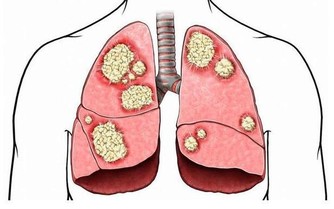

1、身體長期、嚴重缺乏維生素B2是導致A症、腫瘤的根本原因。

缺乏維生素B2的人容易得A症?

流行病學認為A症具有遺傳性,這其實是個錯誤的結論。真正的原因是,父母與子女在飲食結構上具有高度相似性,父母愛吃辣的,經常上火,處於缺乏維生素B2的狀態,那麼子女也必定愛吃辣的,也會缺乏維生素B2,即使子女以後與父母分開了,他(她)的飲食習慣也會保留下來,所以,與父母得相同的病就不足為奇了。

為什麼常吃五穀雜糧的人不易得A症呢?

現在你應該明白了吧,其實是五穀雜糧中(主要在皮、殼上)所含的維生素B2起了作用,如果把皮和殼都去除了,效果就會大打折扣。有些人常吃複合維生素,認為自己不會缺乏維生素B2,實際上,複合維生素中所含的B2遠遠不能滿足人的日常需求,必須單獨補充維生素B2。